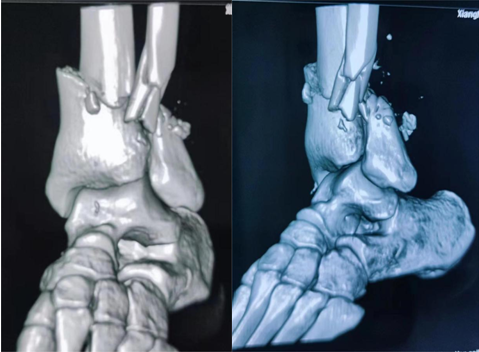

抱着最后的希望邓先生被送到了骨二科,医务人员立即予以开通绿色通道急诊完善术前检查。检查中李杨发现,邓先生伤口在小腿远端,踝关节上方呈环形离断,整只脚畸形仅有部分表皮相连,胫腓骨均粉碎性骨折,还有大量骨质及皮肤缺失,肌肉、肌腱均已断裂,断端完全失去血运,无法活动,更没有知觉,并且伤口周围全是煤灰,污染严重。已经疼得快要休克的邓先生,被紧急送往手术室。

在骨二科医务人员的精心照料下,邓先生伤情很快好转,目前患者断端血运已恢复,皮肤颜色从苍白变为红润,脚趾头已可自主屈伸活动,术后复查患者X线片显示,骨折复位、固定良好。“由衷地感谢湘南学院附属医院骨二科,感谢李杨主任及全体医护人员,挽救了我的断肢。”邓先生激动地说。